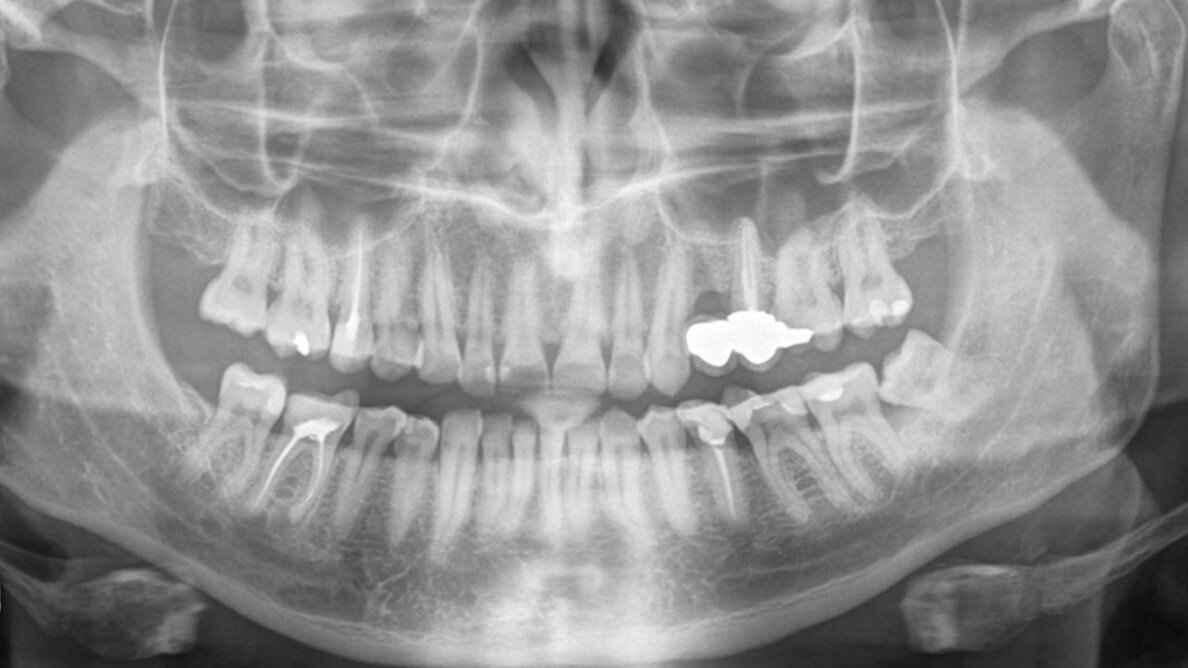

Panoramic radiograph (Image: Paulina Piasta-Kiełkiewicz)

On examination, it was noticed that tooth #26 was tender to cold and sweet. A panoramic radiograph revealed the presence of dental caries penetrating to the pulp chamber (Fig. 1).